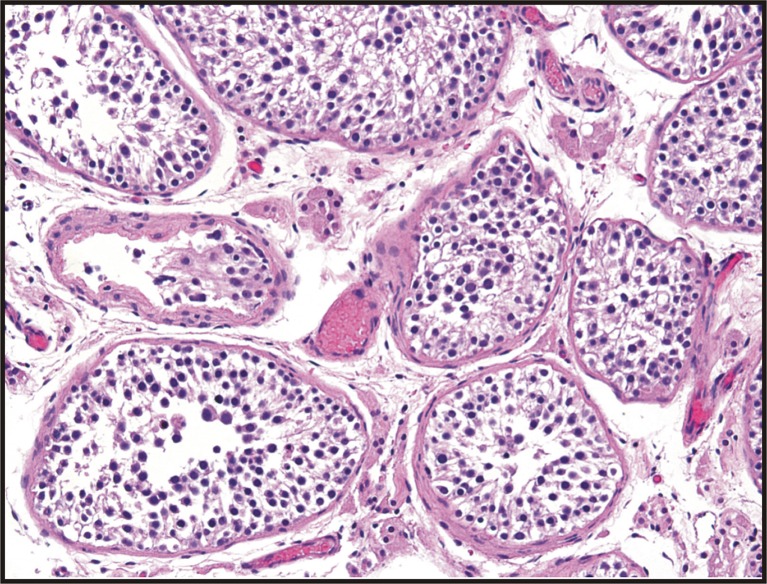

Finally, the patient was scheduled for a testicular biopsy to evaluate sperm production. The biopsy revealed spermatic maturation arrest at the level of the primary spermatocyte (Fig. 2). After discussing the genetic and pathologic results with the patient, he was counseled on the options of adoption and donor sperm for either IUI or IVF.

Fig. 2.

Hematoxylin and eosin stained testicular biopsy specimens demonstrating maturation arrest in a patient with isodicentric Yq mosaicism